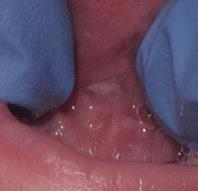

www.smilewonders.com

EDUCATION: Harvard School of Dental Medicine

EXPERTISE: Dr. Jaju is the only pediatric dentist in the MidAtlantic region who has achieved Advanced Laser Proficiency Certification from the Academy of Laser Dentistry and Breastfeeding Specialist Certification.

“During National Children’s Dental Health Month, and every month throughout the year, we want to stress the importance of taking care of your children’s teeth and oral health from the very beginning,” said Dr. Rishita Jaju, owner of Smile Wonders in Reston, Virginia and a board certified

pediatric dentist. “This helps develop healthy habits young so your children will become healthy adults.”

While we won’t say no to all sugars, there are things we can do to help prevent the negatives effects of sugar on young teeth.

1. Brush and Floss Regularly

Brush your child’s teeth or have them brush twice a day with a fluoride toothpaste and a soft-bristled brush. Wait 30-60 minutes after eating sugar or acidic foods before brushing though; brushing too soon can erode softened enamel. Always have your children brush before going to bed because as we sleep our mouths are drier, and there is a risk they won’t make enough saliva to counteract the bacteria caused by sugar left in the mouth. Clean between the teeth daily with regularly flossing. For babies, wipe your child’s gums after each meal.

2. Rinse the Mouth

When you eat, the pH level in your mouth becomes more acidic, which is never good for tooth enamel. The acid can dissolve the minerals that make up the tooth enamel and leave areas vulnerable for bacteria. After eating sugary foods, have your child rinse out or swish their mouth with plain water to counteract the plaque acids.

3. Reduce Snacking

Limit your child’s snacking on sugary foods to short periods of time, rather than snacking throughout the day. This helps reduce acid production in the mouth and lets the saliva levels rebalance in between meals.

4. Eat Healthy Foods

Feed your children healthy foods and limit sugary beverages served with meals and in-between. Vegetables and fruits are important, along with good sources of calcium like milk, yoghurt and broccoli.

5. Get Regular Dental Checkups and Cleanings

Bring your children to their pediatric dentist for regular check-ups and professional cleanings at least twice a year. This will help remove plaque and tartar that just can’t be reached with brushing and flossing.

At Smile Wonders, we prioritize preventive care by creating positive experiences for children and informative visits for parents. Come find out why kids love us and parents trust us for their infants, toddlers and children with various levels of needs and abilities.

Dr.

571-350-3663

11790 Sunrise Valley Drive, Suite 105 Reston, VA 20191

Dr. Rishita Jaju was honored to be selected as a TedX speaker in November, 2023.